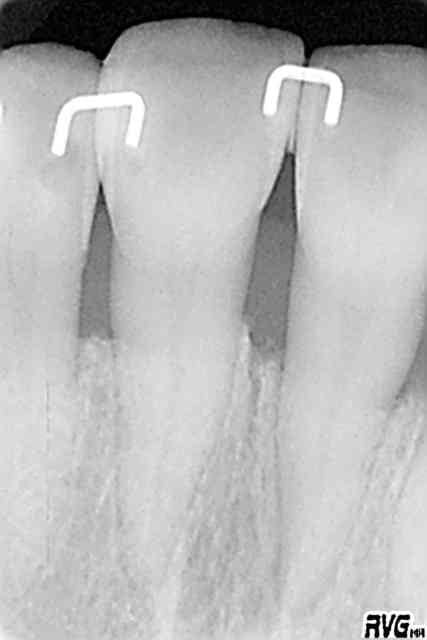

Les attelles d'Abjean j'en pose chaque semaine (ou presque), l'avantage ENOOOOORME par rapport à un "jonc noyé" c'est la rétention 3D que tu n'as pas avec le jonc!

et le délabrement est bcp moindre, en plus quand une attelle lache tu la changes, et pas tout le bastringue!

les miennes tiennent plus de 10 ans...

J'aime beaucoup mon "bridge provisoire" suite à la luxation de la 31 avec fracture de l'apex...^^ elle a tenu 8 ans.

En attendant, ce type de contention transitoire pendant une phase de guérison parodontale après TT ortho (suite aux migrations dentaires) est idéale à mon avis.

3) tu fais une gorge horizontale reliant les 2 points de contact jusqu'à la dentine (prof 1 mm) fraise HL 008

4) un léger avant trou à la fraise boule 008 aux extrémités de la gorge (komet H 009)

5) forage basse vitesse prof 1 à 2 mm les puits doivent être le plus parallèle possible (dans le tiers proximal de la dent à distance raisonnable de la pulpe ;-)

6) confection de l'attelle grâce à une pince à bec plat fine modifiée qui te permet de faire toutes les tailles d'entre-axe

7) essayage et puis souvent réessayage et scellement ou collage si tu en as.

C'est comme cela que Le Pr José Abjean nous l'a appris...à la fac.

C'est joli, mais je trouve que sur les radio, les trous sont plus prodonds que la contention et je trouve cela invasif vs fil ou contention classique. Pour quelques cas bien précis, ok, mais pas trop fréquente l'indication non ?